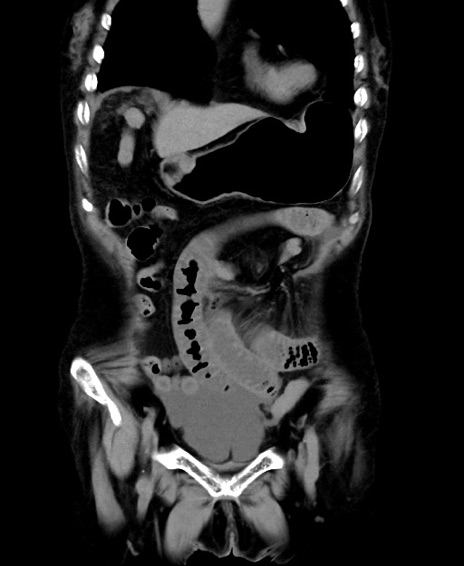

症例40(冠状断像)他院1日前

【症例】90歳代女性

【主訴】腹痛・嘔吐

【現病歴】 食欲低下、嘔吐があり昨日他院受診。肺炎と診断され入院となる。入院後より腹部全体に圧痛あり。胃管留置され経過みていたが、症状持続するため、

当院転院となる。

【既往歴】胸椎圧迫骨折、胆石症

【身体所見】腹部:中央に激痛あり、圧痛あり、反跳痛不明

【データ】WBC 17100、CRP 18.82

冠状断像